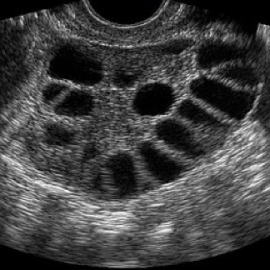

- يجب مراقبة النساء اللواتي يستخدمن هذا الدواء مخبرياً وبالأمواج فوق الصوتية لتقليل خطر حدوث فرط استجابة المبيض والحمل المتعدد وذلك لأنه أشد تحريضاً للإباضة من الأدوية الفموية .

تعتبر كل حالة سواء كانت جماع مؤقت أو حقن داخل الرحم أو إخصاب خارج الجسم مستقلة ويجب أن تراقب بشدة بتحليل مستوى الاستروجين وبالأمواج فوق الصوتية لتقليل احتمال الخطر ولتحديد زمن الإباضة بدقة .

هو حقن تحت الجلد تحرض مبدئياً ثم تثبط الإفراز الدماغي ل LH , FSH وتستخدم في الإخصاب المساعد خارج الجسم لتحسين عدد الجريبات وذلك بمنع الجريب الكبير من التطور .

يعطى هذا العلاج مع تحريض الإباضة عند بلوغ الجريبات حجم 13 – 14 ملم .